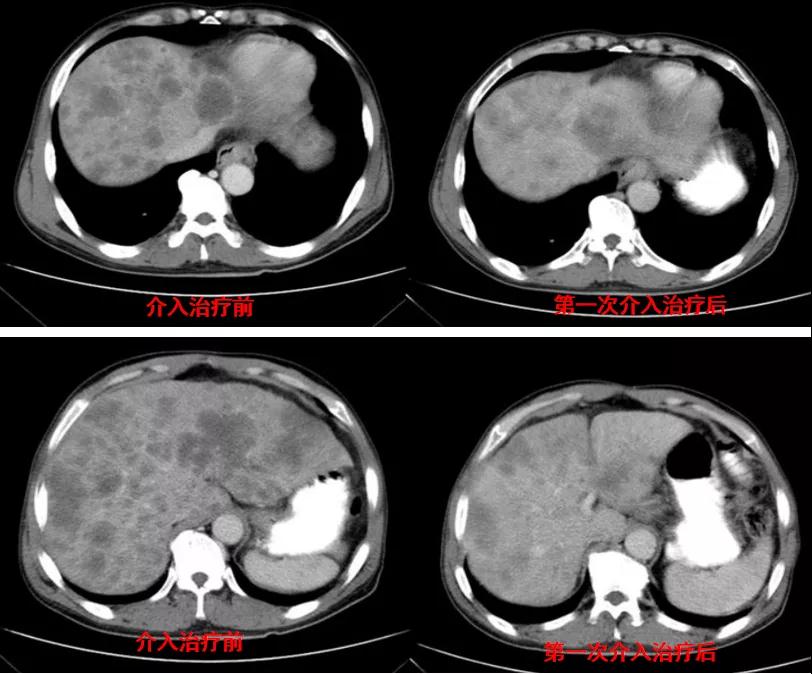

腹部CT检查(2020年11月10日):贲门胃底占位,肝内多发转移灶,腹主动脉旁多发淋巴结肿大,见图1。

图1

诊治经过:2020年11月25日患者行经皮动脉化疗灌注栓塞术(铂类+氟尿嘧啶);2020年11月30日免疫组化及基因检测结果为:ERBB-2扩增(9倍),VEGFR未突变,MSI微卫星低度不稳定,错配修复蛋白部分缺失(dMMR),MSH2(+弱),MLH1(-),MSH6(+),PMS2(-),CDX2(-),Villin(+),CK8/18(+),Ki67(5%+),CD56(-),Syn(-),CgA(-);患者为HER2阳性,患者肝脏病灶很多,残余正常肝脏体积小,需要寻找对肝功能影响小且抗瘤效果明显的治疗,因此联合吡咯替尼进行系统治疗。2020年12月14日复查结果提示肝脏病灶明显缩小(PR)。结果见图2。

图2